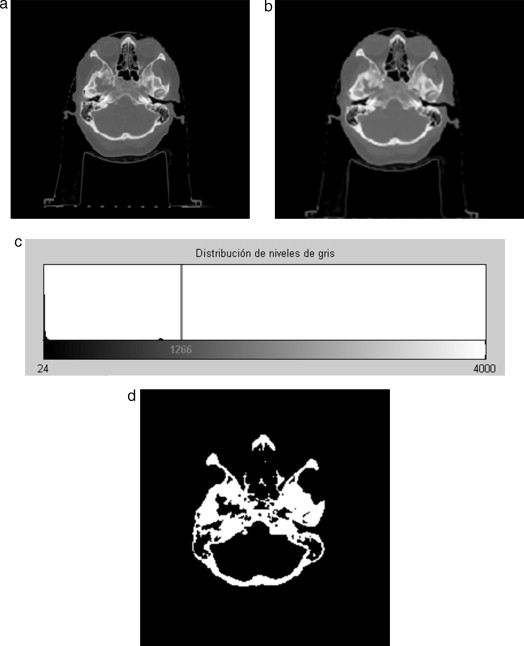

En la figura 22 se presenta la segmentación del cráneo en imágenes de TC en formato DICOM, 256 slices , tamaño de corte de 512 × 512 pixels, voxel spacing: 0,98 × 0,98 × 1,0 mm. Para obtener un valor umbral que distinga el tejido óseo de los demás tejidos, se analizó el histograma global de la imagen, donde claramente se observa que el tejido óseo posee los niveles de gris más altos. En este caso de estudio en espacial, los voxels de la imagen de entrada menores a un umbral de valor 1.266 fueron convertidos a negro, y los voxels con valores mayores al umbral fueron convertidos a blanco. De este modo, se obtuvo un volumen binario del hueso craneal.

Técnica de umbralización aplicada a TC. (a) Vista original de un corte axial de ...

Figura 22.

Técnica de umbralización aplicada a TC. (a) Vista original de un corte axial de TC. (b) Imagen filtrada con difusión anisotrópica. (c) Histograma de imagen b. (d) Imagen binaria resultante de umbralizar imagen b con un umbral de 1266.